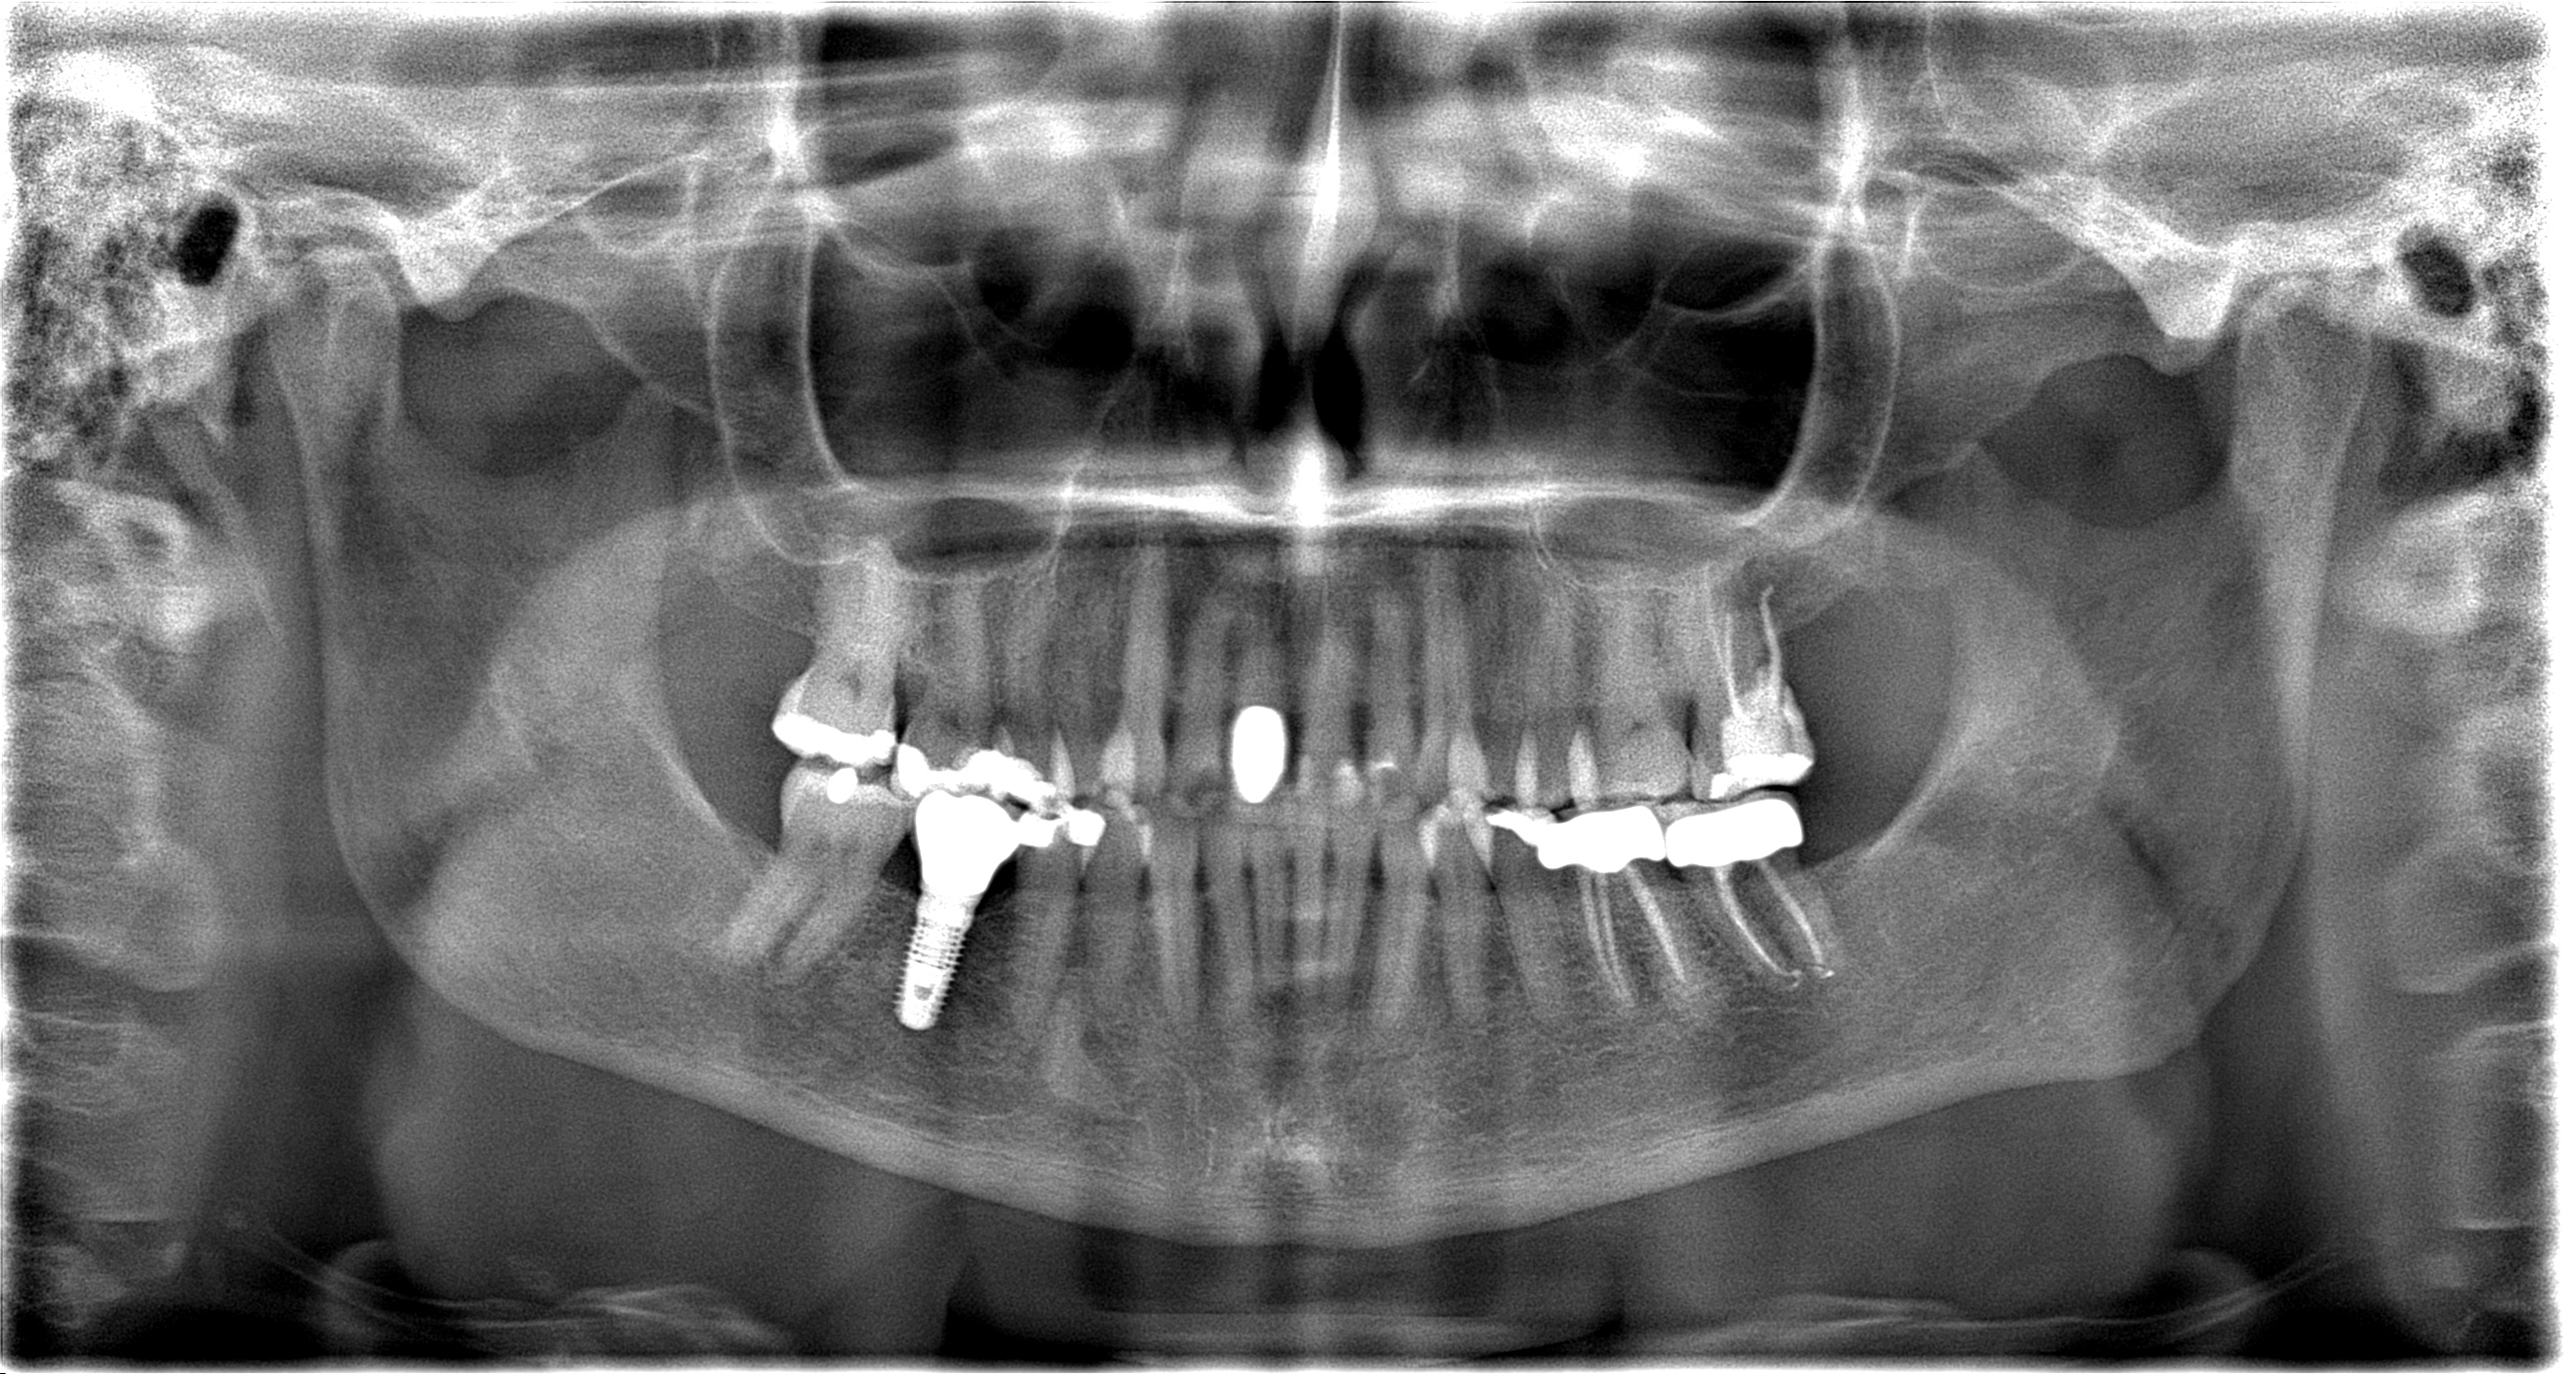

3420_hg_panorama_20190522124635 Veröffentlicht 10. Oktober 2019 am 2789 × 1488 in 3420_hg_panorama_20190522124635